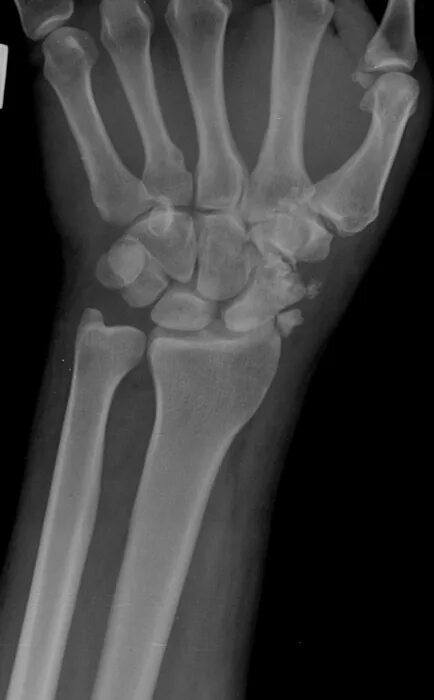

Разработка лучезапястного сустава после перелома